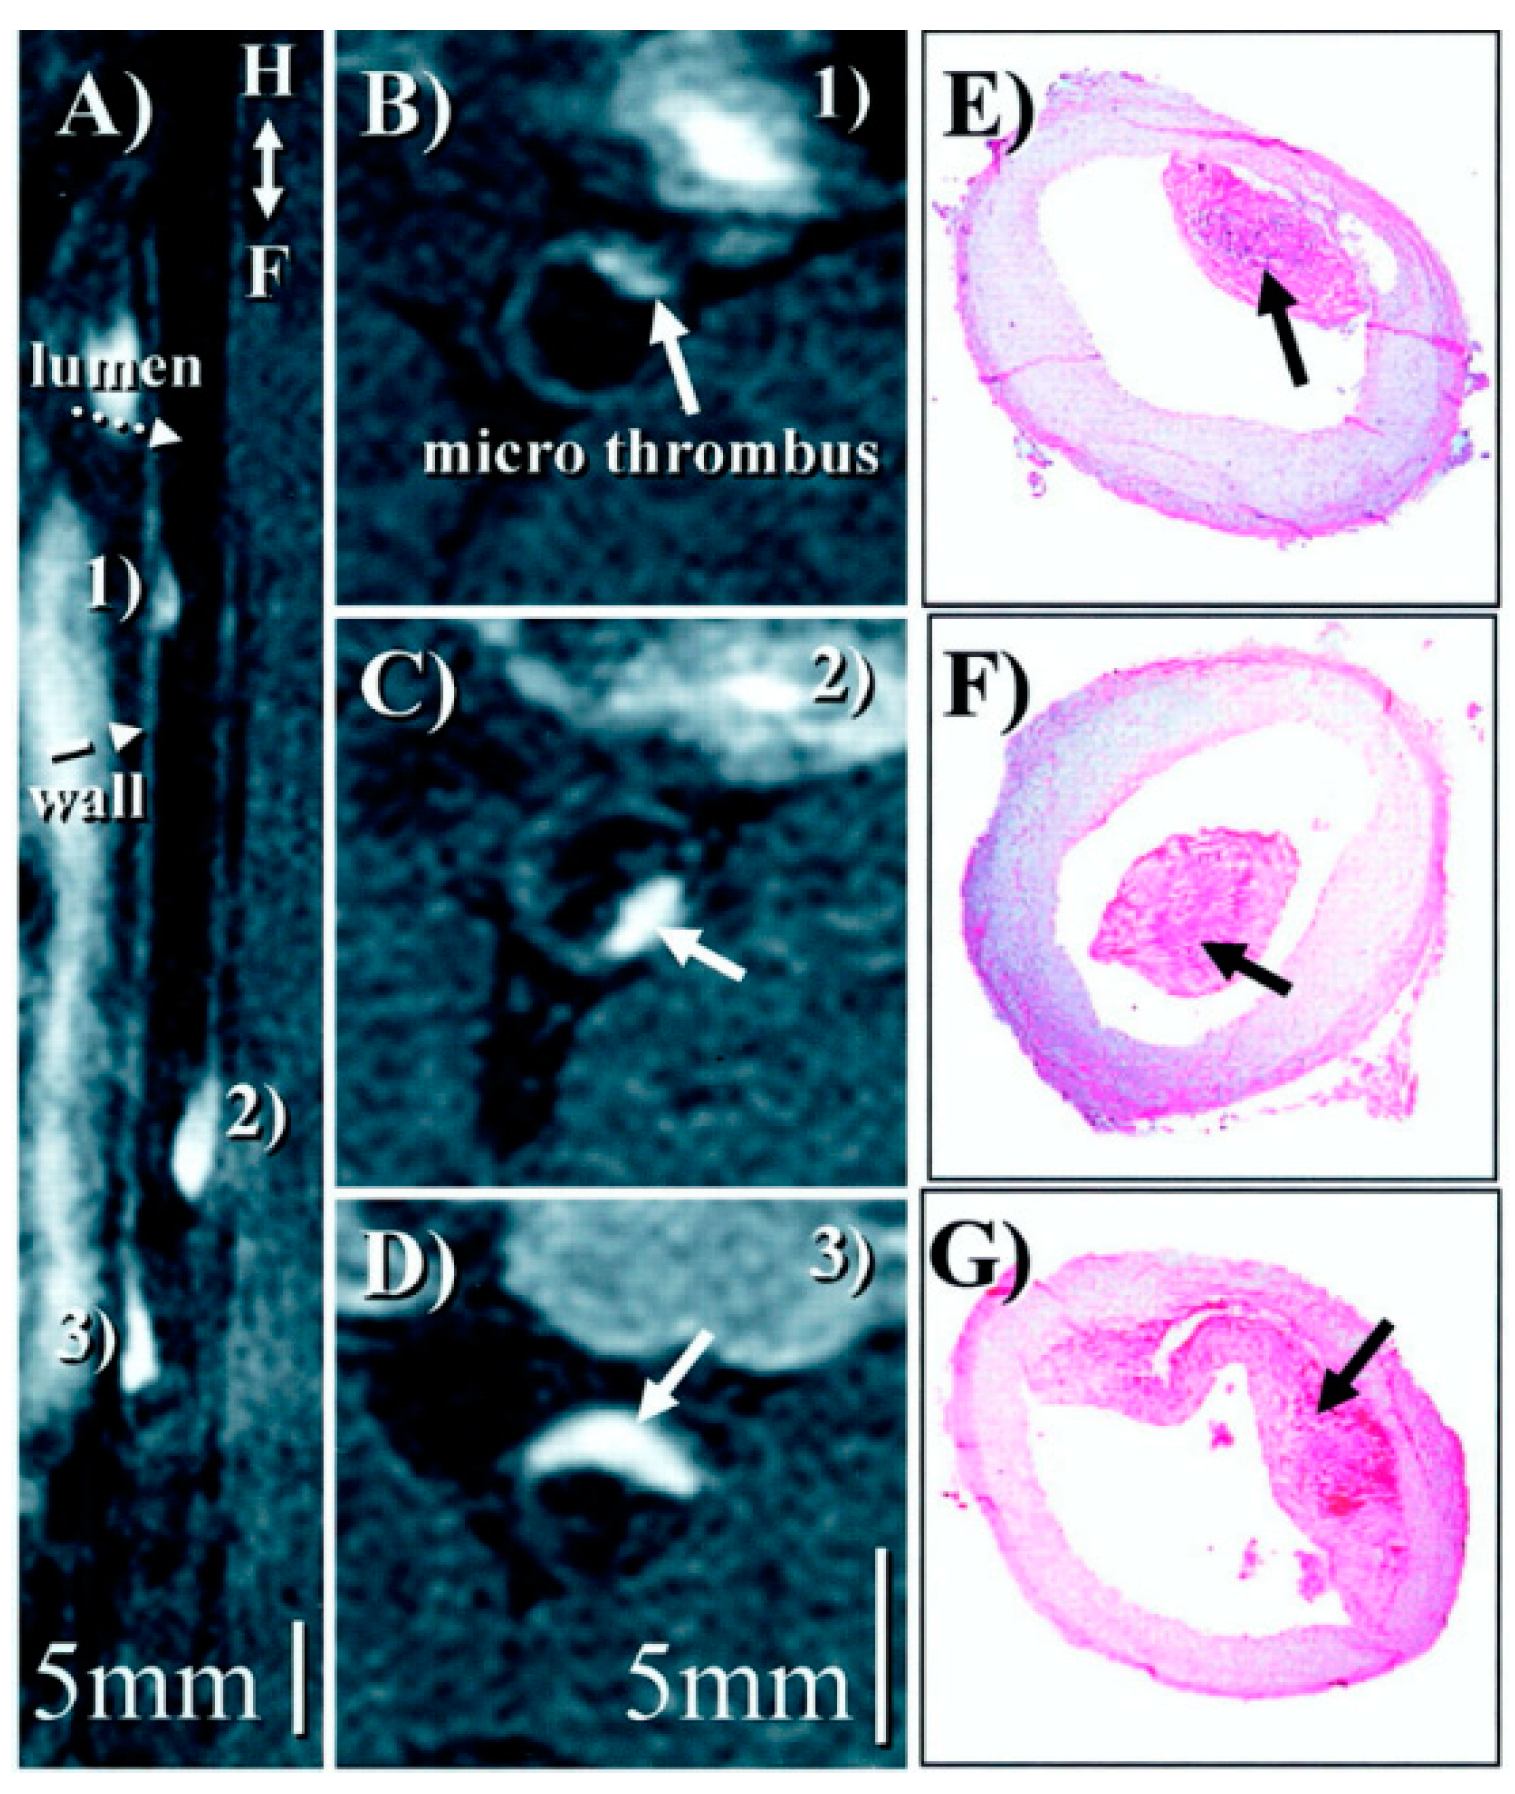

- Phinikaridou, A.; Andia, M.E.; Saha, P.; Modarai, B.; Smith, A.; Botnar, R.M. In vivo magnetization transfer and diffusion-weighted magnetic resonance imaging detects thrombus composition in a mouse model of deep vein thrombosis. Circ. Cardiovasc. Imaging 2013, 6, 433–440. [Google Scholar] [CrossRef]

- Andia, M.E.; Saha, P.; Jenkins, J.; Modarai, B.; Wiethoff, A.J.; Phinikaridou, A.; Grover, S.P.; Patel, A.S.; Schaeffter, T.; Smith, A.; et al. Fibrin-Targeted Magnetic Resonance Imaging Allows In Vivo Quantification of Thrombus Fibrin Content and Identifies Thrombi Amenable for Thrombolysis. Arterioscler. Thromb. Vasc. Biol. 2014, 34, 1193–1198. [Google Scholar] [CrossRef]